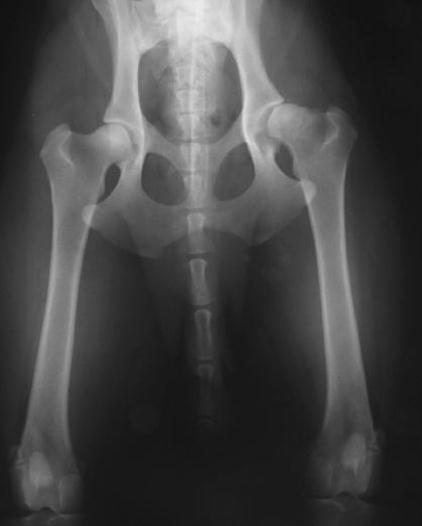

Therefore other views with radiographic stress techniques may be required, as these attempt to quantify maximal dislocation of the femoral head from the acetabulum (see figure 1). In this way a distraction index, a subluxation index, and a dorsolateral subluxation score can be calculated. Radiographic examination for these measurements can be performed from eight months of age, and several studies have suggested that they remain constant after this age.

Two views of a 2.5-year-old male Border collie. left – standard extended radiograph right – stress radiograph allowing measurement of Subluxation Index (note laterodorsal laxity of the right hip, which appeared to be in a normal position in the standard view).